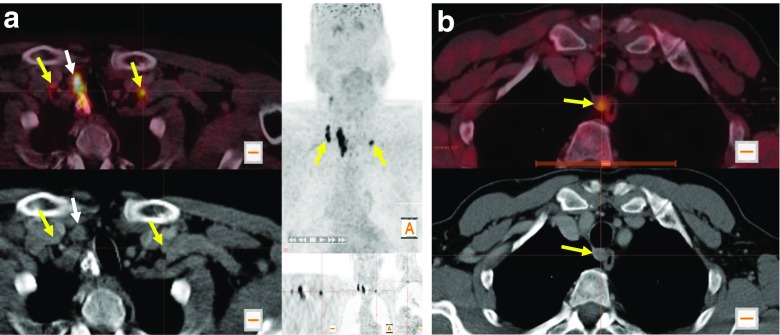

[18F]DOPA PET/CT showed increased DOPA decarboxylase activity in the primary tumour of 28 patients with a maximum SUV (SUVmax.) of 10.5 ± 4.2 (mean ± standard deviation; representative examples are shown in Fig. 1a, b). One patient presented with bilateral suspicious thyroid nodules. Both nodules revealed increased DOPA decarboxylase activity (Fig. 1c). However, there was no evidence of increased DOPA decarboxylase activity in the primary tumour in only four patients. Preoperative LN staging with [18F]DOPA PET/CT showed N0 in 20 patients, N1a in 1 patient, and N1b in 11 patients. In 6 of the patients with stage N1b, [18F]DOPA showed bilateral suspicious LN in neck regions and in one patient showed suspicious LN in the superior mediastinum outside the neck region (Figs. 2a and 3b).

Fig. 2.

Initial [18F]DOPA PET/CT examinations in (a) a 61-year-old male patient with increased DOPA uptake in right and left level IV LNs (yellow arrows), while neck ultrasonography showed suspicious lymph nodes only on the right side, and (b) a 72-year-old male patient with increased DOPA uptake in a lymph node at lower level VI that was not been seen with neck ultrasonography

After surgery and in relation to the results of the postoperative histological tissue analysis, [18F]DOPA detected 88% of the primary MTCs. Patients with no evidence of increased DOPA decarboxylase activity in the primary tumour were exclusively those with T1a tumour stage. Concerning the LN staging, [18F]DOPA detected overall 27 of 41 regional LN detected on histology. [18F]DOPA had a higher sensitivity in detecting lateral LN (19 of 26) than central LN (8 of 15; 73% and 53%, respectively; Table 2). The sensitivity of [18F]DOPA PET/CT was significantly higher than that of ultrasonography in regional and patient-based LN assessments (Table 2). In addition, in six of eight patients with histologically verified bilateral involvement of cervical LN, [18F]DOPA showed bilateral LN with increased DOPA decarboxylase activity (Fig. 2a).